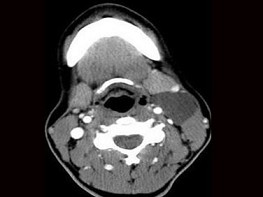

| 十产岁患者,女性,因颈前正中包块3年入院,查体:颈前胸锁乳突肌前缘上1/3外可触及一圆形包块,囊性,无压痛,不随吞咽上下活动。 |

6.CT检查结果见下图,本患者应考虑为 ( )![]() ![]() ![]() ![]() |

| 正确答案:6.C;7.E |